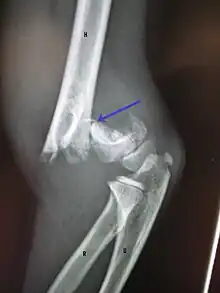

Definitive diagnosis of humerus fractures is typically made through radiographic imaging. For proximal fractures, X-rays can be taken from a scapular anteroposterior (AP) view, which takes an image of the front of the shoulder region from an angle, a scapular Y view, which takes an image of the back of the shoulder region from an angle, and an axillar lateral view, which has the patient lie on his or her back, lift the bottom half of the arm up to the side, and have an image taken of the axilla region underneath the shoulder.[9] Fractures of the humerus shaft are usually correctly identified with radiographic images taken from the AP and lateral viewpoints.[12] Damage to the radial nerve from a shaft fracture can be identified by an inability to bend the hand backwards or by decreased sensation in the back of the hand.[5] Images of the distal region are often of poor quality due to the patient being unable to extend the elbow because of pain. If a severe distal fracture is suspected, then a computed tomography (CT) scan can provide greater detail of the fracture. Nondisplaced distal fractures may not be directly visible; they may only be visible due to fat being displaced because of internal bleeding in the elbow.[7]

A fracture of the greater tuberosity as seen on AP X ray

A fracture of the greater tuberosity of the humerus